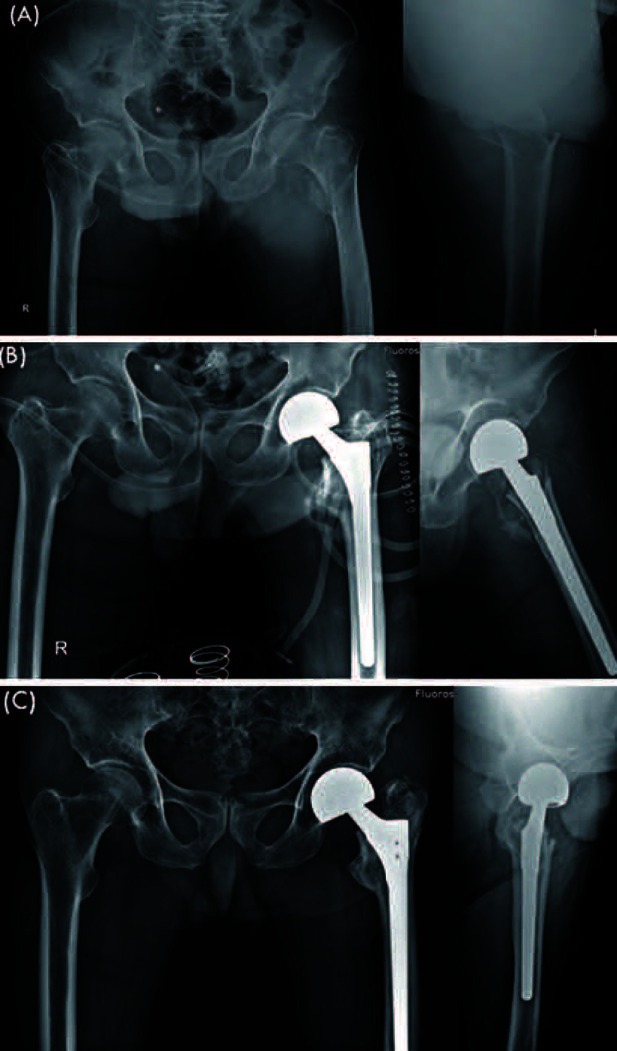

Purpose: The aim of this study was to compare short-term results from use of the direct anterior approach (DAA) and the conventional posterolateral approach (PLA) in performance of bipolar hemiarthroplasty for treatment of femoral intertrochanteric fractures in elderly patients.

Materials and methods: A retrospective review of 100 patients with intertrochanteric fractures who underwent bipolar hemiarthroplasty was conducted. The PLA was used in 50 cases from 2016 to 2019; since that time we have used the DAA in 50 cases from 2019 to 2021. Measurements of mean operative time, blood loss, hospitalization period, and ambulation status, greater trochanter (GT) migration and stem subsidence were performed. And the incidence of complications was examined.

Results: Operative time was 73.60±14.56 minutes in the PLA group and 79.80±8.89 minutes in the DAA group (P<0.05). However, after experiencing 20 cases using DAA, there was no statistically difference in operative time between two groups (P=0.331). Blood loss was 380.76±180.67 mL in the PLA group and 318.14±138.51 mL in the DAA group (P<0.05). The hospitalization was 23.76±11.89 days in the PLA group and 21.45±4.18 days in the DAA group (P=0.207). In both groups, there were no progressive GT migration, intraoperative fractures or dislocations, although there was one case of infection in the PLA group.

Conclusion: Although use of the DAA in performance of bipolar hemiarthroplasty required slightly more time in the beginning compared with the PLA, the DAA may well be an alternative, safe surgical technique as a muscle preserving procedure in elderly patients with intertrochanteric fractures.